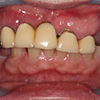

5.装上人工牙齿

拍摄装入种植齿以后口内的整体印象(模型制作)。根据这个模型制作义齿。然后在支座上装上义齿。